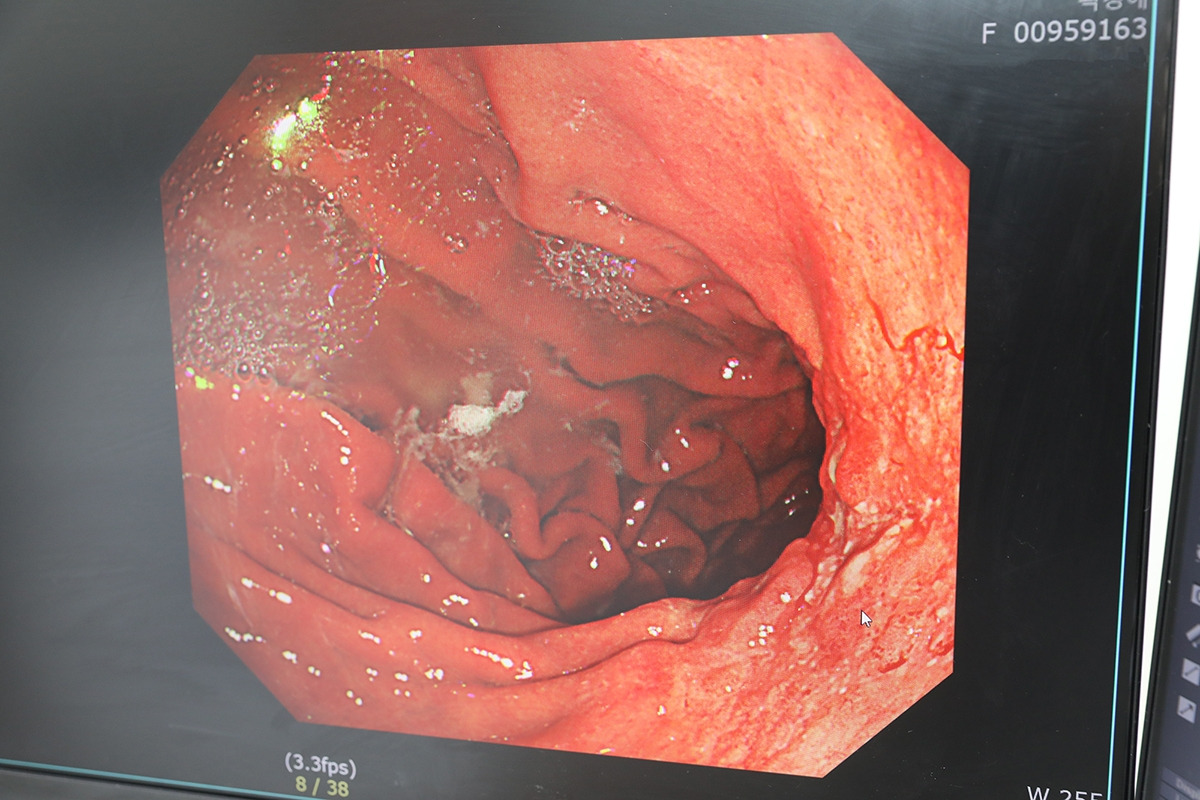

[참고자료]위암환자 내시경 사진.jpg